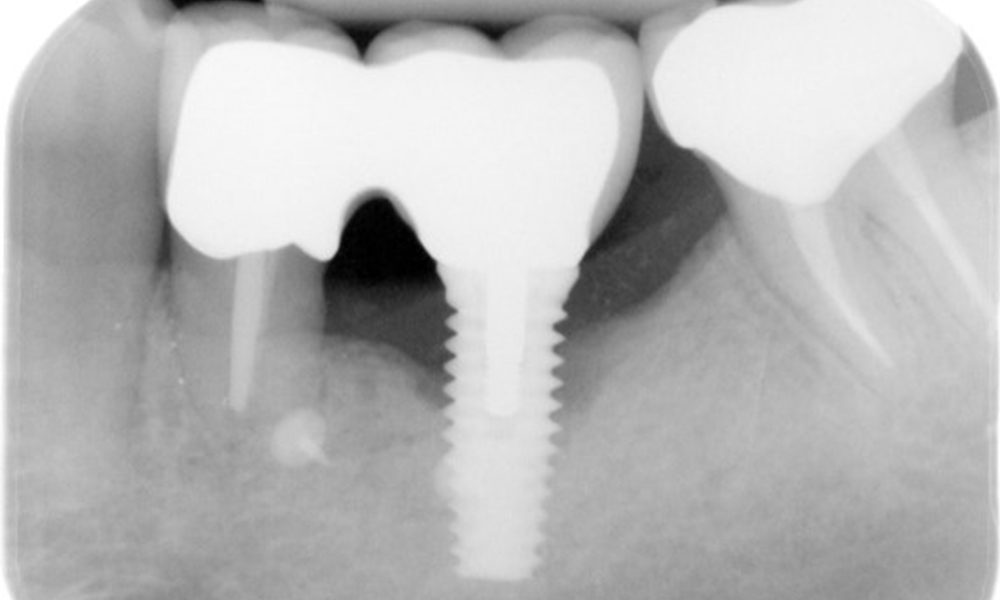

The patient has no particular risk factors with specific dental implications in his medical history. The key factor, therefore, is the requirement in terms of oral health. In this respect, there is evidence of a probing depth of 5 mm at the implant in the 3rd quadrant and, on the X-ray image, increased bone loss. The patient also has currently stable early periodontal disease and two active initial carious lesions.

In terms of instruments, specific procedures are required for use with implants. In order to preserve the surface of the implant while cleaning it effectively, it is essential to choose suitable powders and instruments, such as the targeted use of air polishing devices with special periodontal tips. Which powder is most suitable can be determined according to the needs and risk. For example, in addition to the appropriate degree of abrasion, dietary requirements (including sugar-free, low-salt) may also be taken into account.